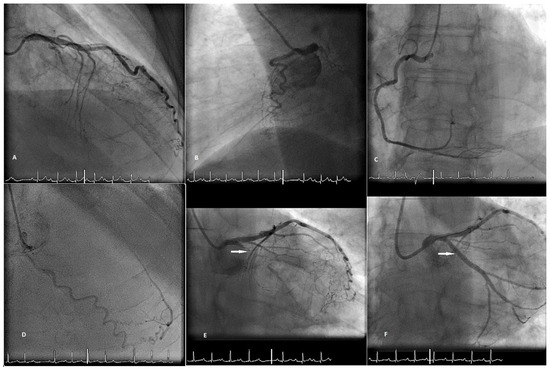

When performing revascularisation of a chronic total occlusion, contralateral injection is essential to visualise the distal bed of the occluded vessel, adding to procedural success. Here we describe a case of antegrade recanalisation of a left anter...